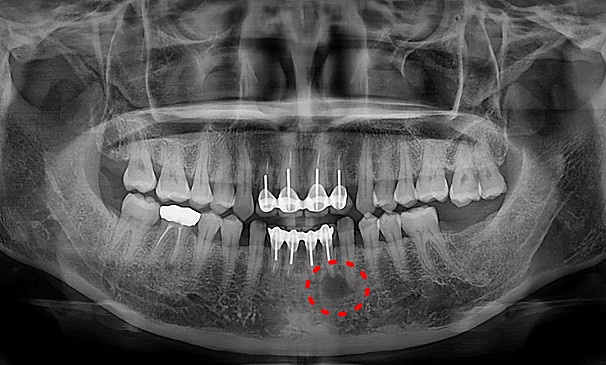

이OO님 전후사진 | 치료 기간 : 3개월 후

치료 전

치료 후

뿌리염증제거술